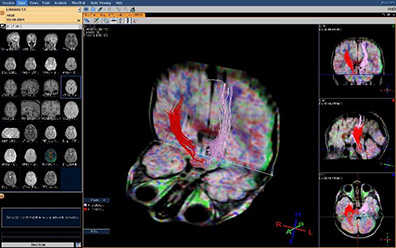

Рис 2.B. – МР – трактография: выраженная ассимитрия кортико-спинальных трактов.